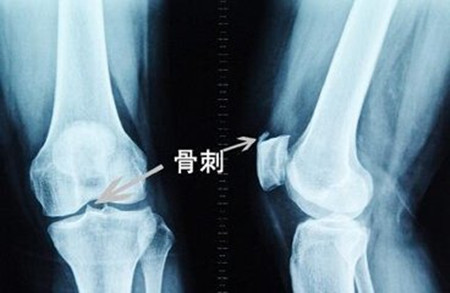

骨质增生是一种多发病,常见病。膝关节骨质增生就是其中的一种常见症状,膝关节骨质增生也称为增生性退行性关节炎。它并不是关节普通炎症,而是一种软骨长期退化病变。膝关节骨质增生在我们日常生活中还是很常见的,那膝关节骨质增生该怎么办呢?>>>点击咨询,诱发膝关节骨质增生的原因有哪些

早期的膝关节退变会有轻微的疼痛不适感,可以通过改变生活习惯,加强股四头肌肌力训练等来治疗。中期关节退变会出现膝关节肿大、罗圈腿、疼痛加重等,除早期的治疗方法外,还需要加用药物治疗,可以行关节镜微创手术治疗。晚期关节退变就是重度骨性关节炎了,疼痛更重,畸形更明显,可采取人工膝关节置换。